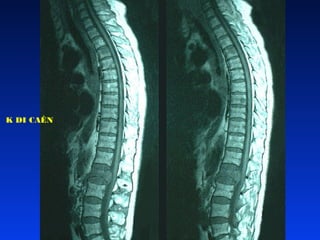

K DI CAÊN

CAÙC BÖÔÙU AÙC TÍNH •Nguyeân phaùt: böôùu EWING, sarcome xöông • Thöù phaùt: böôùu EWING, böôùu xöông, ung thö maùu, beänh HODGKIN, nguyeân baøo thaàn kinh, böôùu cô vaân, böôùu WILM’S • Ñieàu trò: böôùu nguyeân phaùt: caét boû toaøn boä neáu coù theå ñöôïc